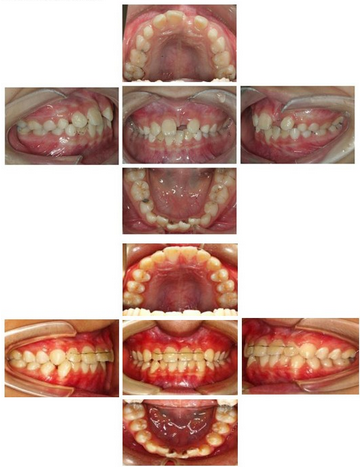

早期矫治前后合像对照:

固定矫治前后合像对照: